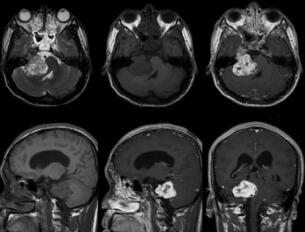

图1 右侧桥小脑角区见一分叶状占位性病变,大小约3.4cm×3.2cm,以等T1等T2为主的混杂信号。增强扫描呈明显不均匀强化,小脑、第四脑室受压,双侧侧脑室、第三脑室增宽

男,27岁,一个月前发现间断性右耳鸣,每天约10次左右,每次持续约1分钟左右,眼前一过性黑矇,每次持续4~5秒,每日约10次左右,偶有间断性右侧头痛、头晕。患者病来无发热、无抽搐、无明显听力下降,饮食正常,睡眠良好,二便正常。双侧瞳孔等大正圆,对光反射灵敏,眼球向各方向活动自如,眼位居中,右侧慢相眼震阳性。面纹对称,鼓腮、露齿面纹对称,无张口受限。深浅感觉检查未见明显异常。右侧膝跳反射(+)、踝阵挛(+),右侧巴宾斯基征(+);左侧正常。